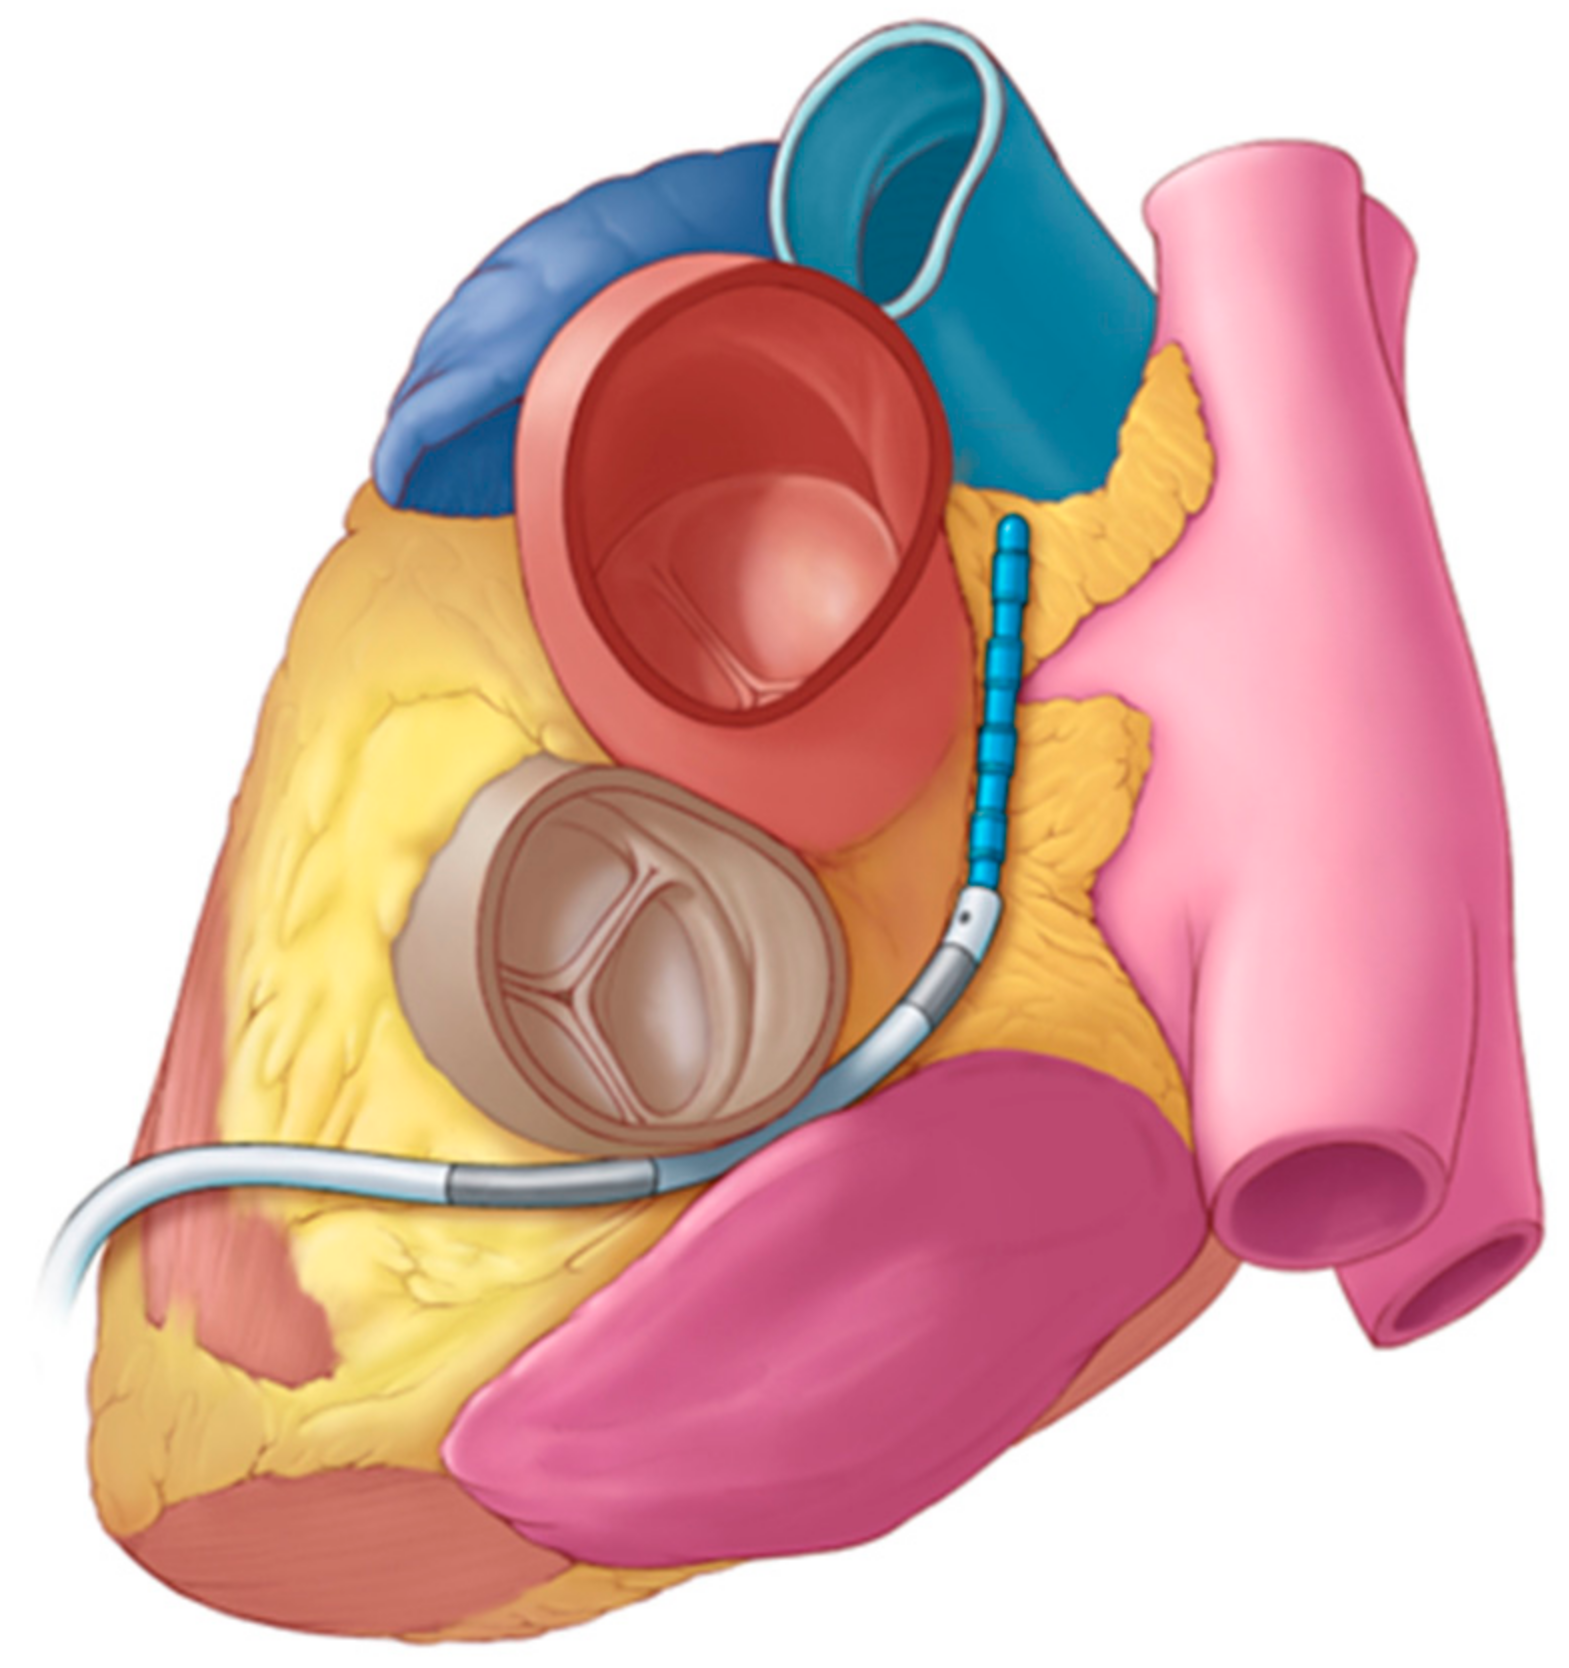

2.1. Ablation System Designs

2.5. Porcine Study—Catheter Access and Navigation